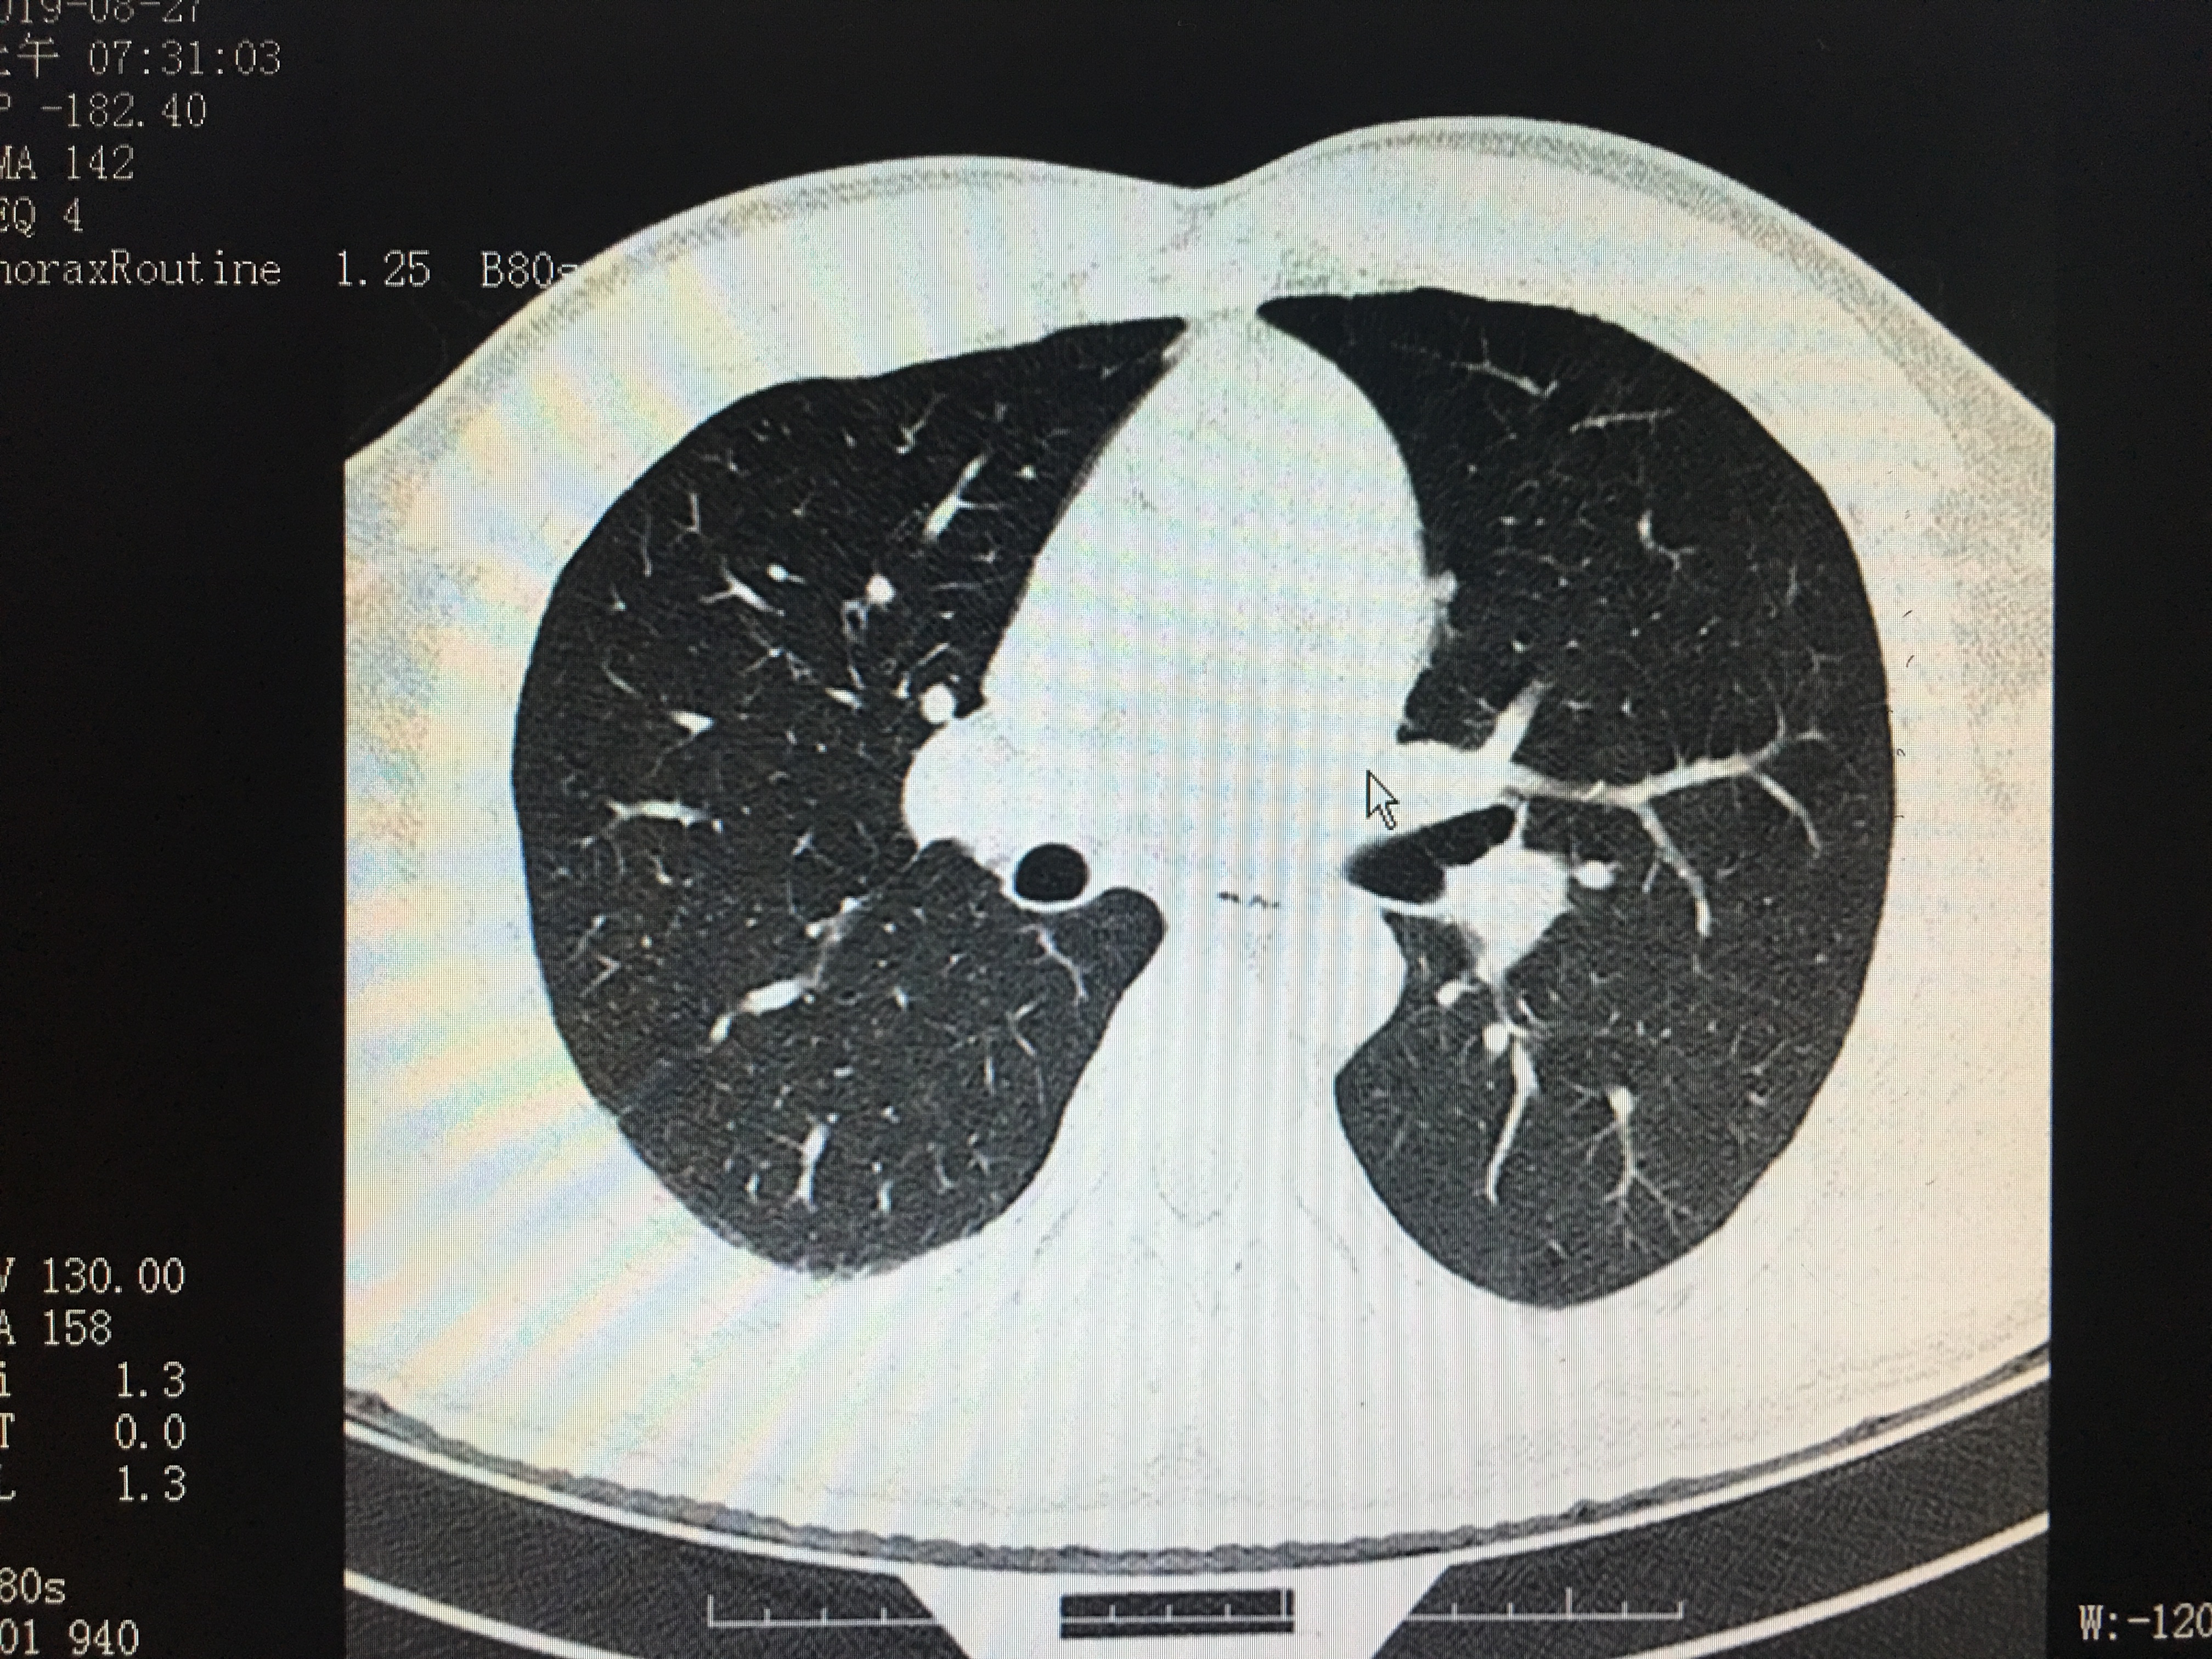

正常的胸部CT成像

相信这两个图像的区别很多人都能明显的看出来,第一张图明显比第二张清晰:图2显示模糊,伪影较多,就好像手机拍照时手抖了一样,而图一清晰更容易看出是否有病变存在。如图中,图一可明显看清双肺存在散在的结节灶,而第二张图因为没屏住气,形成的伪影比较多,就算有结节灶也未必能看出来。而肺部的结节灶大部分为良性的,一般建议定期复查,部分恶性病灶进展时通过复查对比可发现。